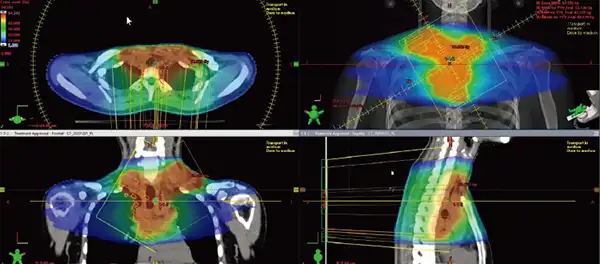

強度変調回転放射線治療(VMAT)とは

強度変調回転放射線治療(VMAT:Volumetric Modulated Arc Therapy)とは、リニアックが回転しながら連続的に放射線を照射することで、腫瘍の形状や位置に合わせて放射線の強度や照射範囲を細かく調整する治療法です。従来のIMRT(強度変調放射線治療)と比べて、照射時間が短縮されるとともに、より高精度な線量分布が得られるため、腫瘍への集中治療と正常組織への影響軽減が同時に実現できます。これにより、患者さんの負担が少なく、効率的な治療が可能となっています。

VMATを使った放射線治療

従来の放射線治療では、重要な臓器に対する線量制限のため十分な線量の投与ができなかった腫瘍に対する放射線治療が、現在は可能となってきています。

両側に広がる病変に対して、従来は十分な放射線治療ができませんでしたが、VMATを用いることで治療を行うことができるようになってきました。